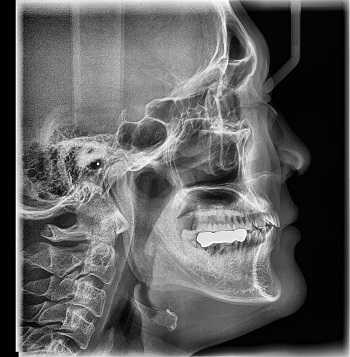

Рентген

Наиболее старый и привычный метод визуализации человеческого тела. Применяют рентген повсеместно, от хирургии до стоматологии. Метод прост и понятен: человека облучают особыми лучами, которые легко проходят сквозь мягкие ткани и задерживаются в твёрдых. Благодаря этому принципу, на фотоплёнку или датчик, расположенные на противоположной от источника лучей стороне, передаётся изображение, а в распоряжение врача попадает рентгенография или рентгеноскопия.

Главные плюсы такого обследования: быстрота и стоимость. Рентгеновскими аппаратами оснащены практически все больницы, процедура проходит быстро и стоит недорого.

Главные минусы: облучение и качество изображения. При проведении рентгенографии пациент облучается, а картинка получается двумерной. Врач с трудом может разглядеть внутренние органы по отдельности, поскольку их тени перекрывают друг друга. Также невозможно детально разглядеть хрящевую ткань и мозг. Хрящи практически не задерживает лучи, мозг надёжно закрыт черепной коробкой. Для их исследования рентгенография не подойдёт.

Наиболее эффективно будет проводить рентгенографию при повреждениях костей, суставов и зубов.

Рентгенография

Принцип работы рентгеновского аппарата заключается в том, что рентгеновские лучи, проходя через разноплотную среду исследуемой области, по-разному ослабляются: более плотная костная ткань в значительной степени поглощает рентгеновское излучение, менее плотная подкожно-жировая клетчатка ослабляет его в небольшой степени, а воздух, содержащийся в околоносовых пазухах или легких, не задерживает совсем. Эти неравномерно ослабленные пучки рентгеновских лучей, попадая на светочувствительный слой пленки, формируют рентгенограмму — изображение, которое отображает все структуры исследуемой области, наслаивая их друг на друга. При этом получаемый снимок позволяет определить форму, размеры и строение исследуемой области, выявить или заподозрить структурные нарушения, а исследование в двух или нескольких проекциях позволяет определить локализацию выявленных изменений. Чаще всего рентгенография используется для исследования костей, легких, почек, кишечника.

C самого начала существования этот метод диагностики вызывал у пациентов множество вопросов по поводу воздействия рентгеновского излучения на организм. На сегодняшний день специалисты подтвердили вред рентгена и его способность влиять на развитие нежелательных процессов в организме. Тем не менее, этот метод лучевой диагностики продолжает пользоваться спросом, поскольку требует минимальных затрат.